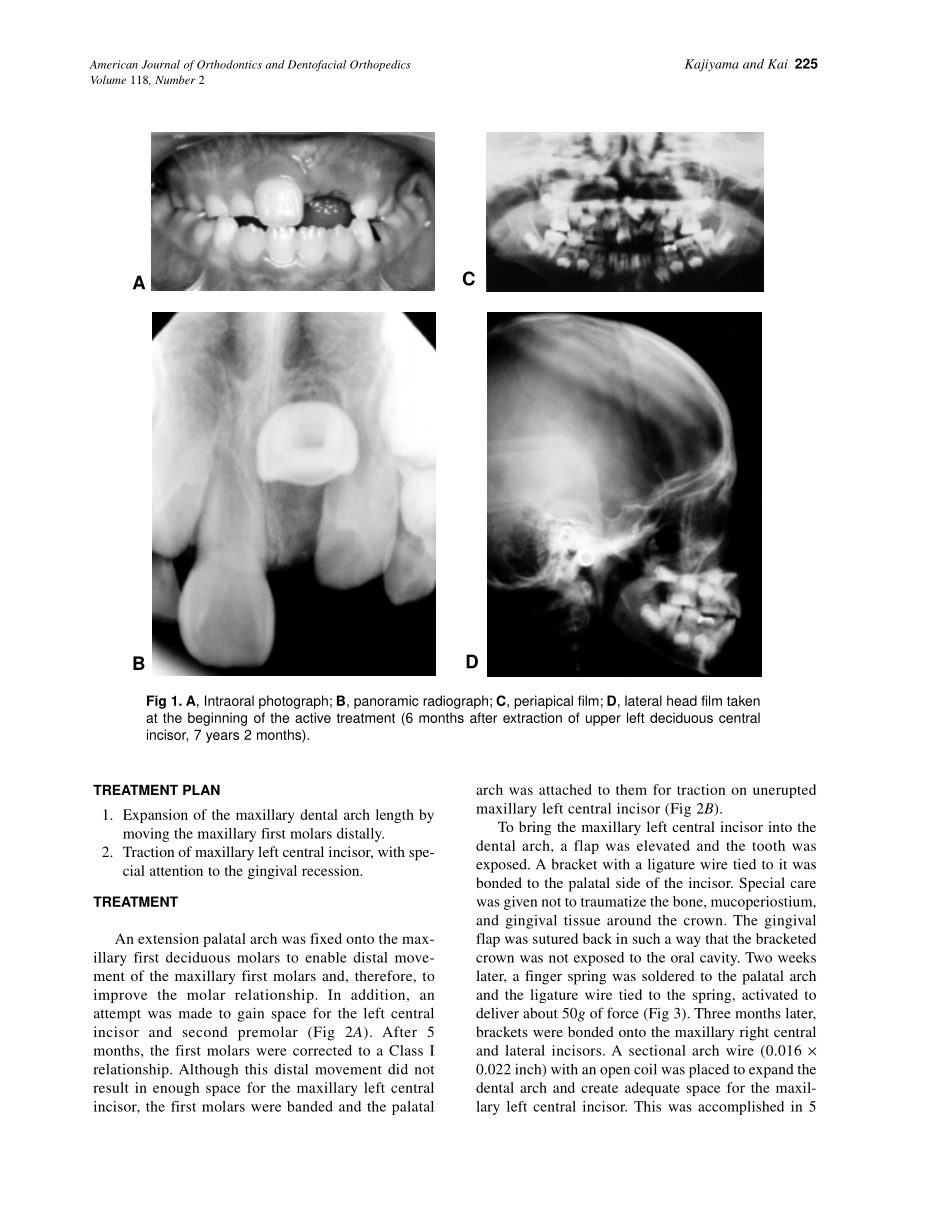

224Uneruptedteethareoftenencounteredinorthodonticpractice.Thetreatmentandprognosisareusuallyinfluencedbyvariousfactors1-3andmayincludeabroadrangeofoptions,frompassiveobservationtoexposurewithtracti...